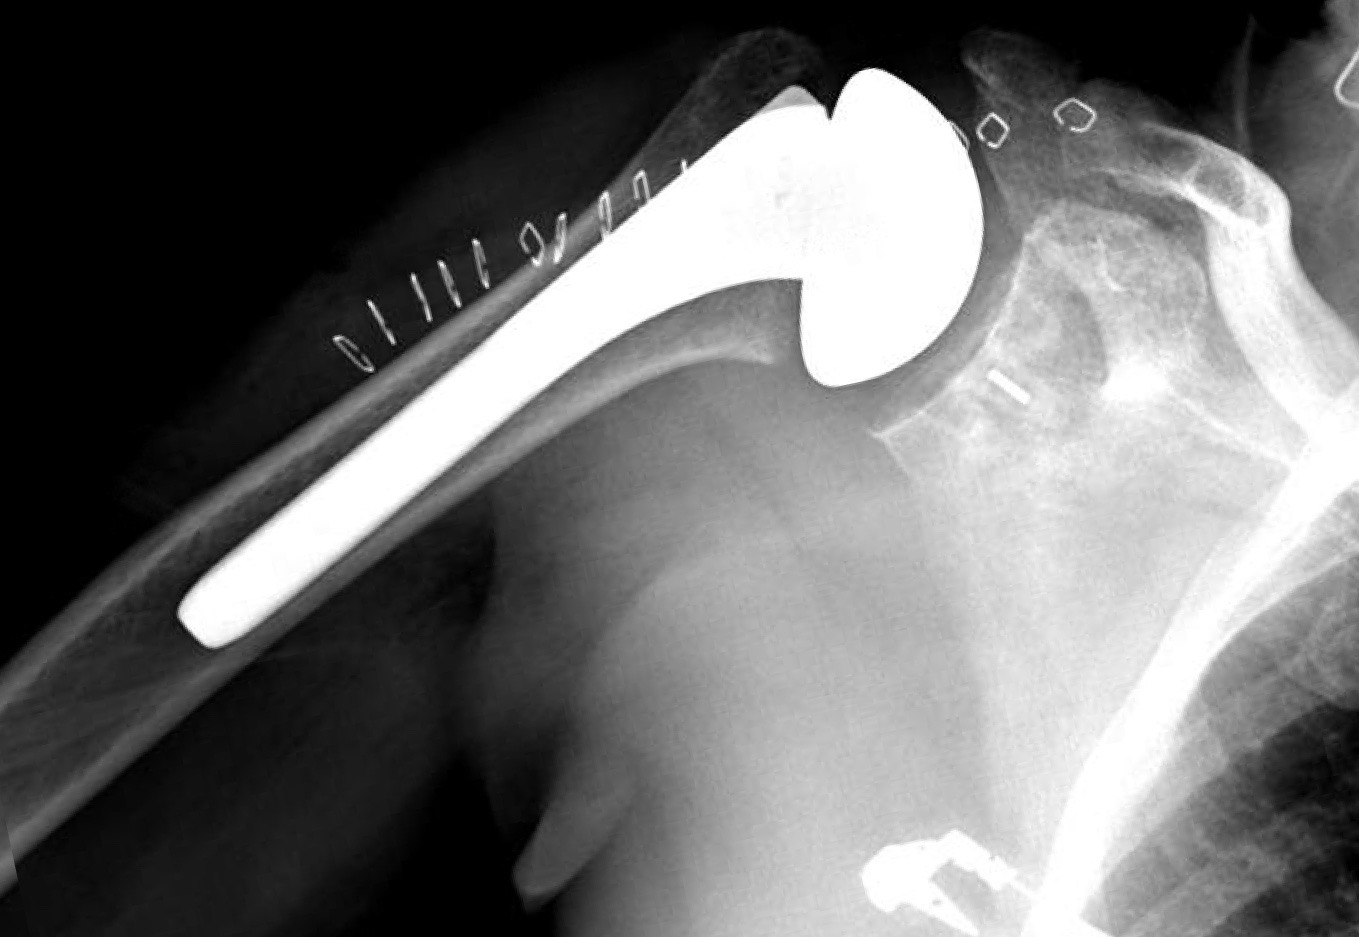

First dislocation is seen above 3 weeks after index procedure

Revision to thicker polyethylene provided stability for a short period of time (2 weeks)